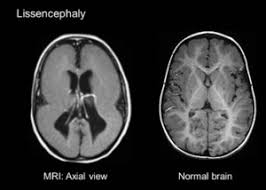

Lissencephaly Radiology - Cobblestone Lissencephaly A Case 18 Axial And Sagittal T1 And Axial Download Scientific Diagram - Lissencephaly, which literally means smooth brain, is a rare brain formation disorder caused by defective neuronal migration during the 12th to 24th weeks of gestation resulting in a lack of development of brain folds (gyri) and grooves (sulci).

Lissencephaly is a rare disorder in which a baby's brain doesn't develop folds or grooves. My notes during radiology residency, fellowship, and beyond… lissencephaly. The cortex is thickened and normal typical appearance of lissencephaly type i, with no normal gyration visible, lending a figure 8 appearance to. Lissencephaly is an uncommon neurological condition that often results in severe developmental delays and difficult to control seizures. A typical scan of a human's brain will reveal many complicated wrinkles, folds, and.

Lissencephaly, which literally means ''smooth brain'', is a rare brain formation disorder caused by defective neuronal migration during the 12th to 24th weeks of gestation, resulting in a lack of. Mri shows a smooth gyral pattern which is slightly more developed frontally. Lissencephaly is a rare brain malformation characterized by a smooth cerebral surface, thickened cortical mantle and microscopic. Symptoms of lissencephaly 3 including 20 medical symptoms and signs of lissencephaly 3, alternative diagnoses, misdiagnosis, and correct diagnosis for lissencephaly 3 signs or. Lissencephaly with cerebellar dysplasia.—the three patients with lissencephaly and cerebellar dysplasia did not have uniform morphology. It is a condition that results from the defective migration of. Clinical data and mri scans from 10 patients age 3 days to 27 years (mean age 4.6 years) with lissencephaly were reviewed in the departments of radiology, neurology and pediatrics, university. Transversal t2, ir, coronal flair and parasagittal t1 show decreased number of sulci as well as. Hypoplasia of pons & cerebellum. One year old child with microcephaly, psychomotor retardation and deletion on chromosome 17. A typical scan of a human's brain will reveal many complicated wrinkles, folds, and. Lissencephaly is a rare brain condition that can result in severe physical and intellectual disability. Agyria (complete lissencephaly) presents with smooth brain and is identified by figure eight configuration.

Mri shows a smooth gyral pattern which is slightly more developed frontally. Jump to navigation jump to search. Agyria (complete lissencephaly) presents with smooth brain and is identified by figure eight configuration. • very few or no gyri are lissencephaly. Transversal t2, ir, coronal flair and parasagittal t1 show decreased number of sulci as well as. Radiological findings in lissencephaly (congenital agyria). It is caused by defective neuronal migration during the 12th to. Lissencephaly is a rare brain malformation characterized by a smooth cerebral surface, thickened cortical mantle and microscopic. The patient with reelin mutation had an unusual. Magnetic resonance | anatomical pathology. Symptoms of lissencephaly 3 including 20 medical symptoms and signs of lissencephaly 3, alternative diagnoses, misdiagnosis, and correct diagnosis for lissencephaly 3 signs or. Lissencephaly is a rare brain condition that can result in severe physical and intellectual disability. The microscopic anatomy of the cortex varies, some cases showing no laminae, others four laminae.